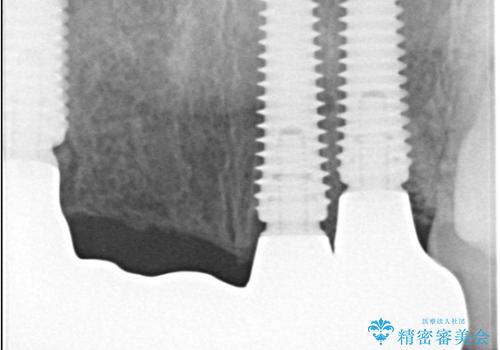

- 歯茎の大きな腫れを主訴に来院された患者様です。前歯5本にはブリッジが装着されていました。レントゲン検査より、右上3番に大きな根尖病巣が認められ、さらに左上1、2番の支台歯にも破折があったため、抜歯を行いました。その後、インプラントを3本埋入し、オールセラミッククラウンのブリッジで補綴しました。

術前のCT画像より、抜歯即時インプラントが可能と判断したため、抜歯と同時にインプラント埋入を行いました。術式にはセミルーナーフラップを用い、唇側の骨吸収を抑える目的でルートメンブレンテクニックを併用しました。

抜歯即時インプラントには、切開量が少なく痛みが出にくいこと、一度の手術で治療が完了するため治療期間を短くでき、患者様の身体的負担も軽減できるという大きなメリットがあります。

今回のケースでも、しっかりと固定が得られたため、手術は1回で終了し、短期間でオールセラミッククラウンまで装着することができました。患者様も術後の痛みはなく、処方した痛み止めも服用されなかったとのことです。